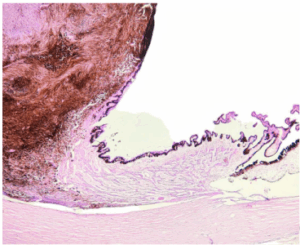

NEOPLASIA QUÍSTICA MUCINOSA DE PÁNCREAS

MELANOMA UVEAL